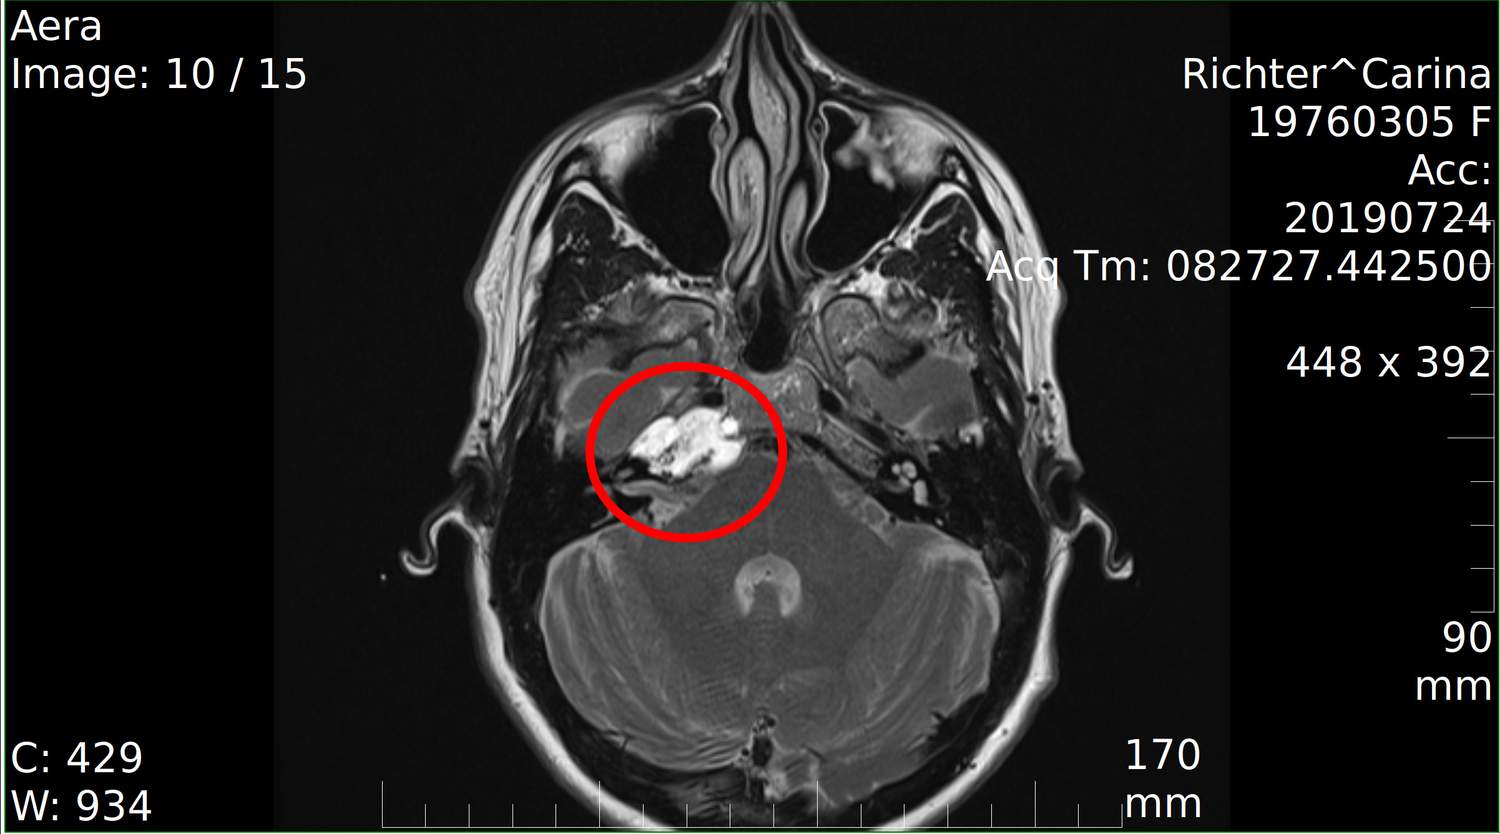

Nach der Diagnose eines Chondrosarkoms am Hirnstamm begann ein intensiver medizinischer Weg. Bereits wenige Tage nach dem Befund folgten MRT- und CT-Untersuchungen. Im Oktober 2019 erfolgte die erste Operation, gefolgt von einer zweiten, komplexen Neurochirurgie im selben Jahr – beide unter Leitung von Prof. Dr. Ewelt. Die Eingriffe waren hochriskant, da der Tumor in unmittelbarer Nähe zu lebenswichtigen Hirnstrukturen lag. Vorübergehende neurologische Ausfälle wie Schluckstörungen, Gleichgewichtsstörungen und Lähmungen traten auf.